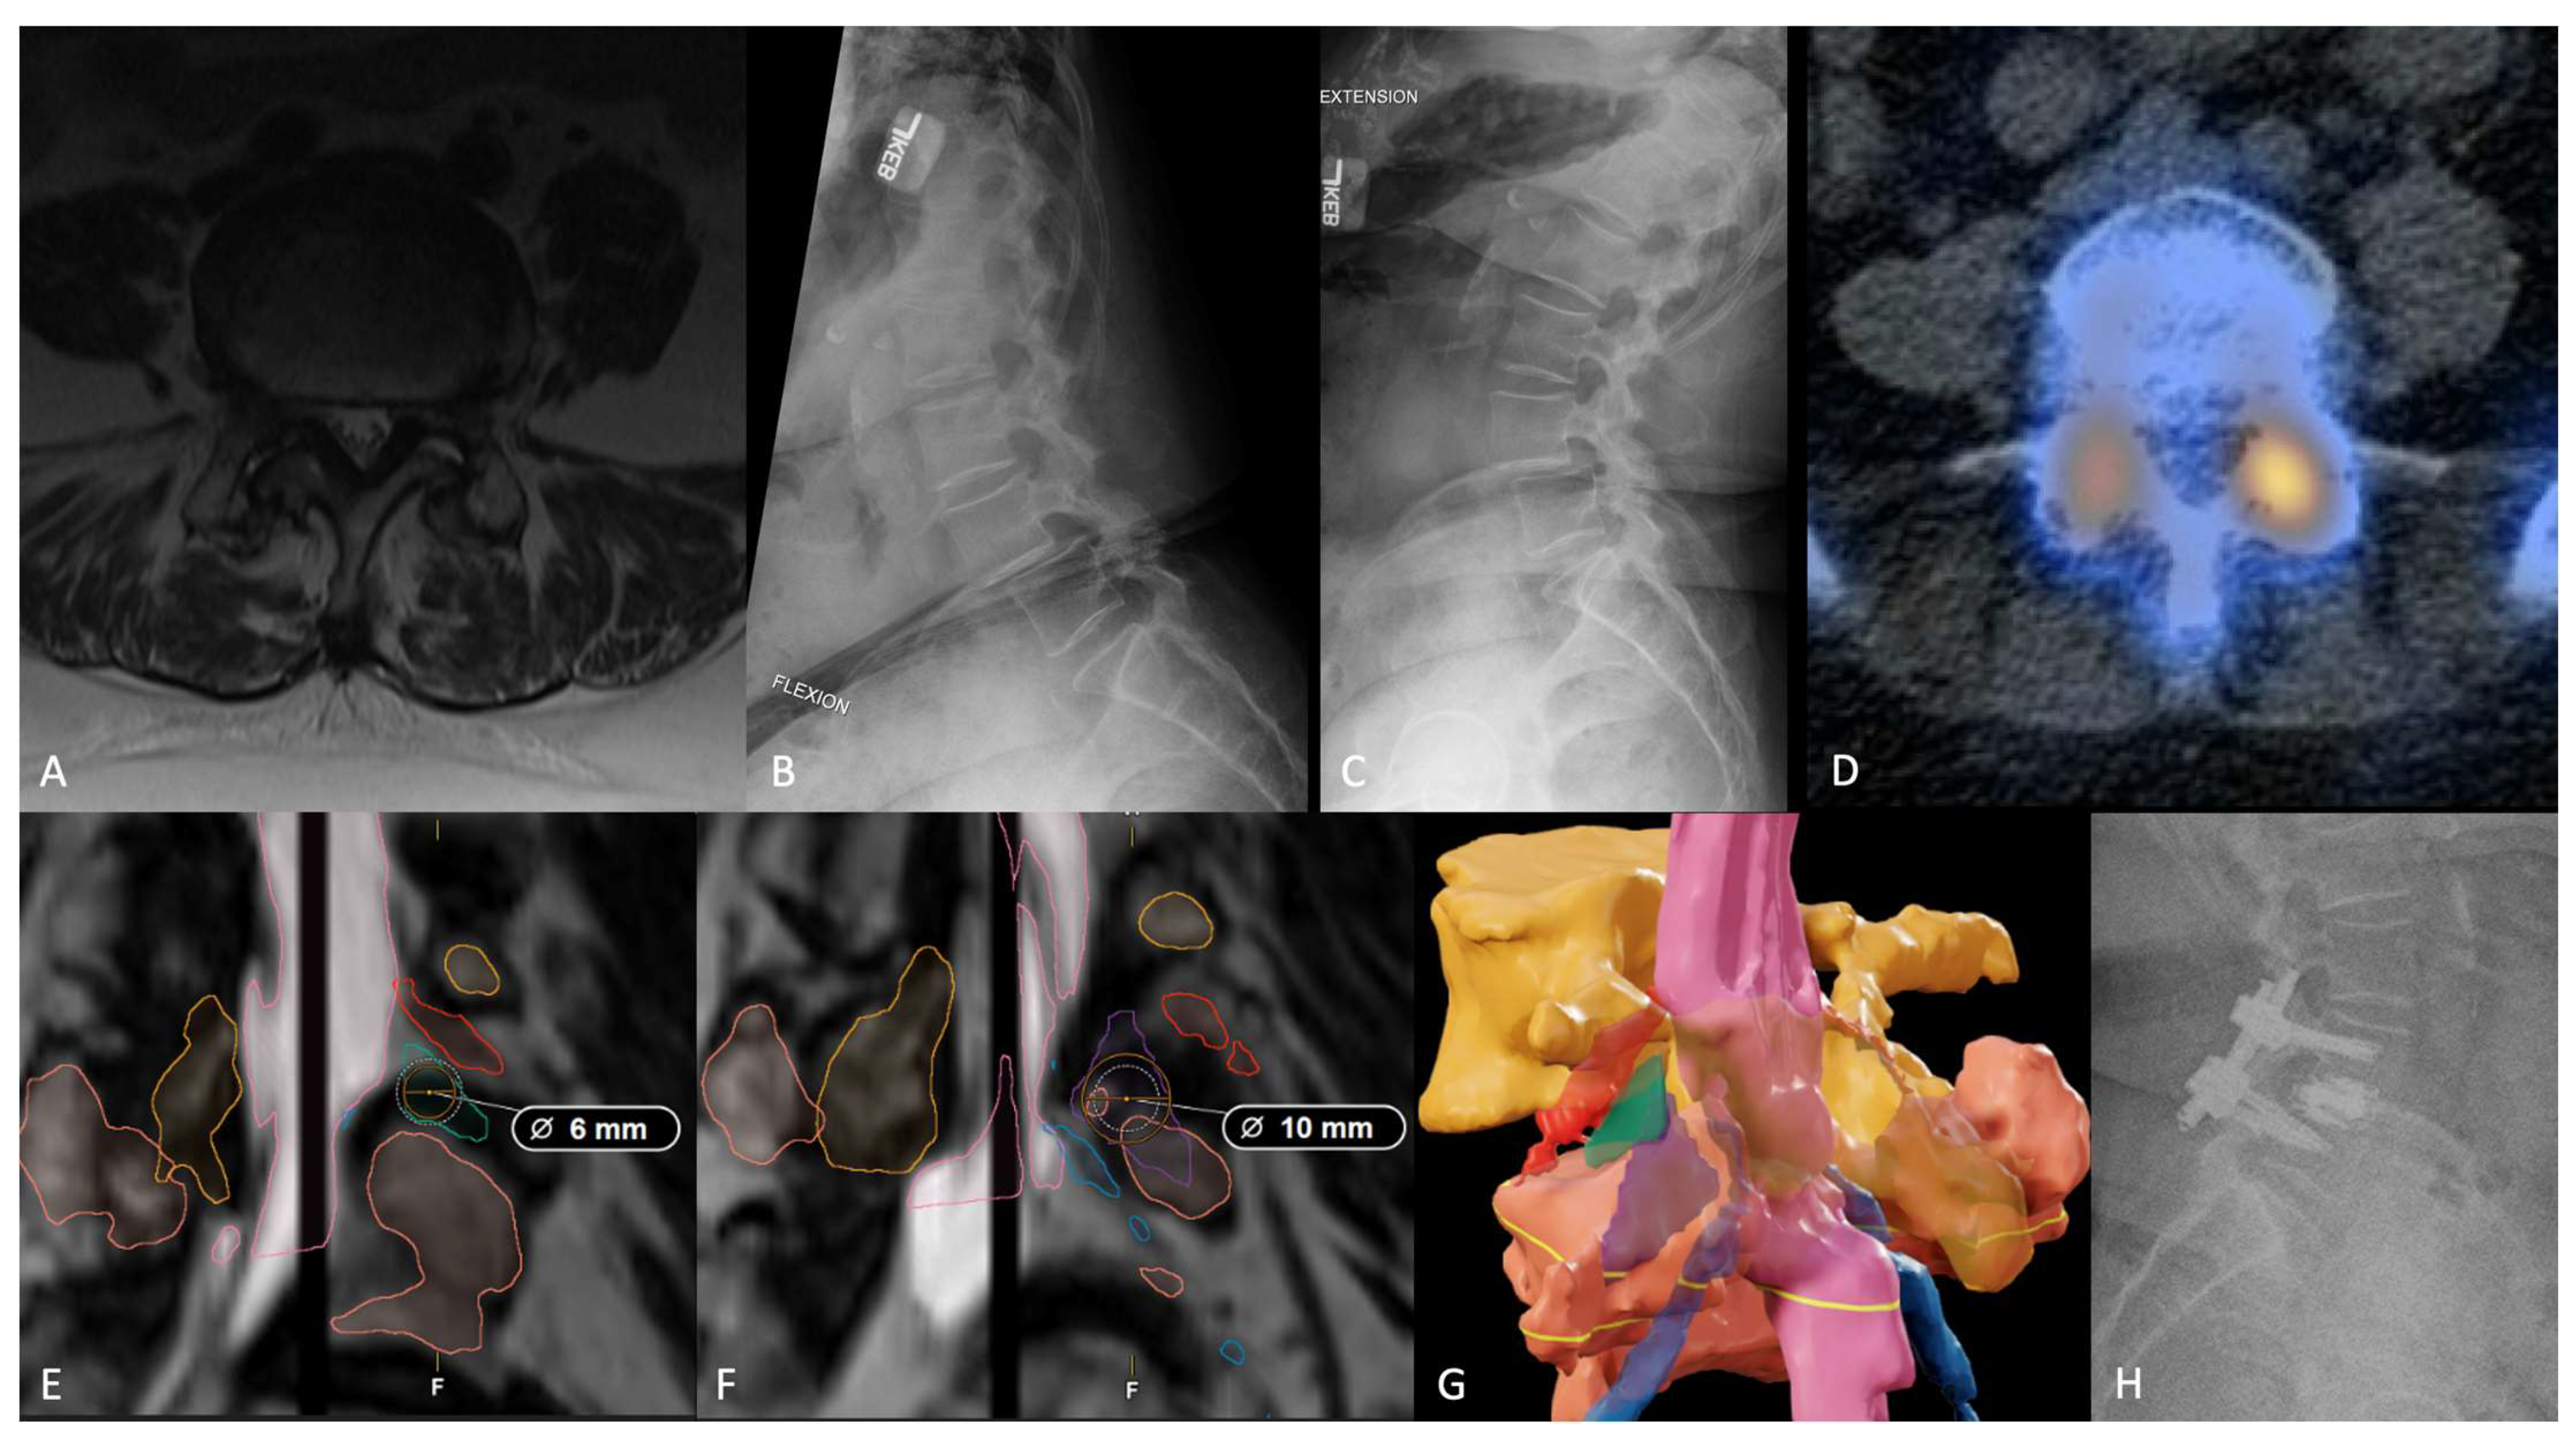

Representative Case

- Tabarestani, T.Q.; Salven, D.S.; Sykes, D.A.W.; Bardeesi, A.M.; Bartlett, A.M.; Wang, T.Y.; Paturu, M.R.; Dibble, C.F.; Shaffrey, C.I.; Ray, W.Z.; et al. Using Novel Segmentation Technology to Define Safe Corridors for Minimally Invasive Posterior Lumbar Interbody Fusion. Oper. Neurosurg. 2023. [Google Scholar] [CrossRef] [PubMed]